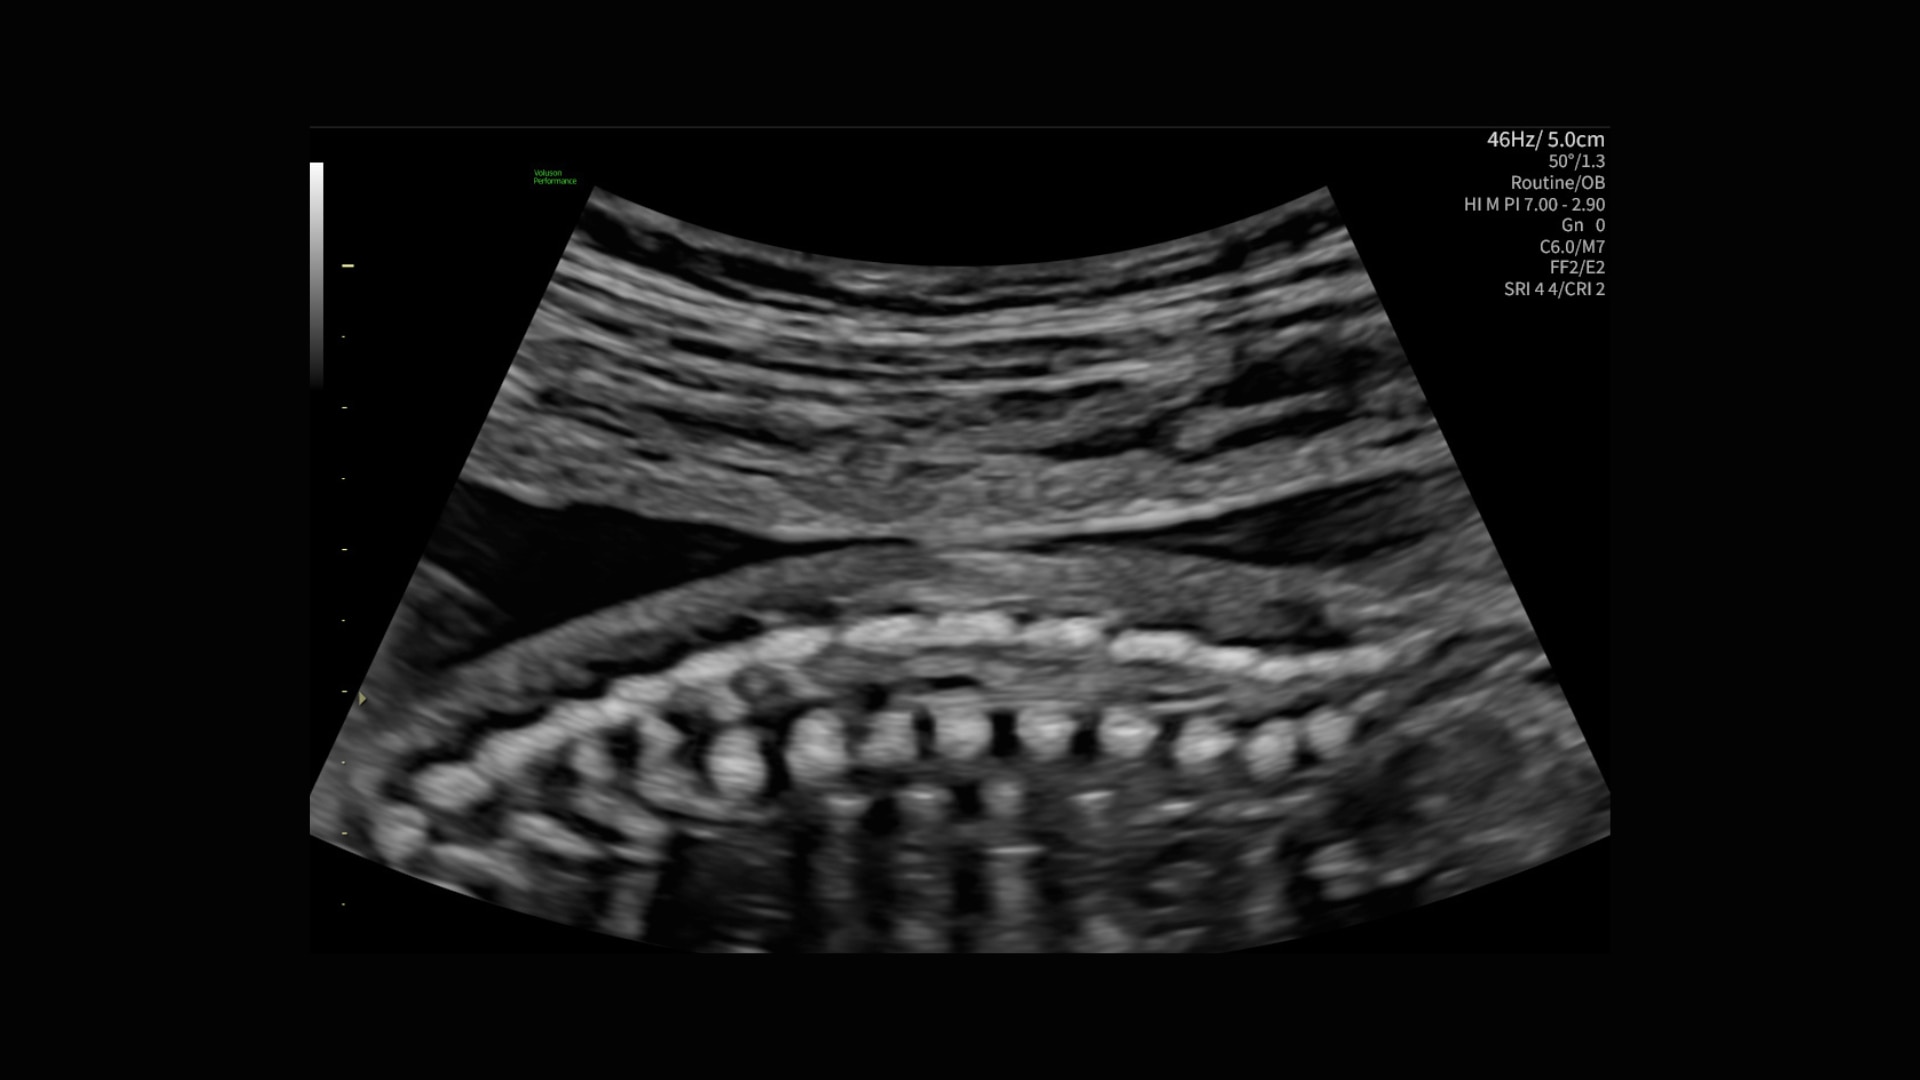

Acquire the coronal view of the spine in 1/2 the time using Spine Trace.